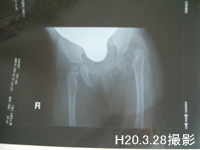

診察の結果は左足股関節脱臼。レントゲンを見ると見事に外れていてしかも外れている左足の臼蓋と骨頭が小さい。外れた時に成長がストップしていたのです。右足とは全然違います。 「かなり前から外れています」 と言われました。

かなり高位脱臼してると言われました。そのあとレントゲン。(注:既にどこかの病院でレントゲンを撮っていたら借りて持っていった方が良いです。私達はすっかり忘れてしまったのでもう一度撮る事になりました。子供の負担を考えたら持参すべきでした。反省・・・。)

3787df94.jpg

そしてレントゲンを見ながら再度鈴木先生と話をしました。

やはりかなり前から外れていると言われました。